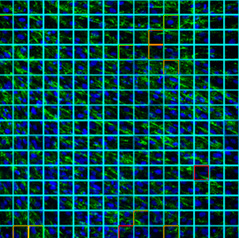

Imatges de cultius de fibroblasts obtingudes amb un microscopi confocal. Esquerra: una mostra de control. Centre: mostra d'un pacient amb miopatia de Bethlem. Dreta: Mostra d'un pacient de la distròfia muscular d'Ullrich. En les tres imatges, la xarxa de col·lagen es mostra en verd i els nuclis dels fibroblasts en blau.